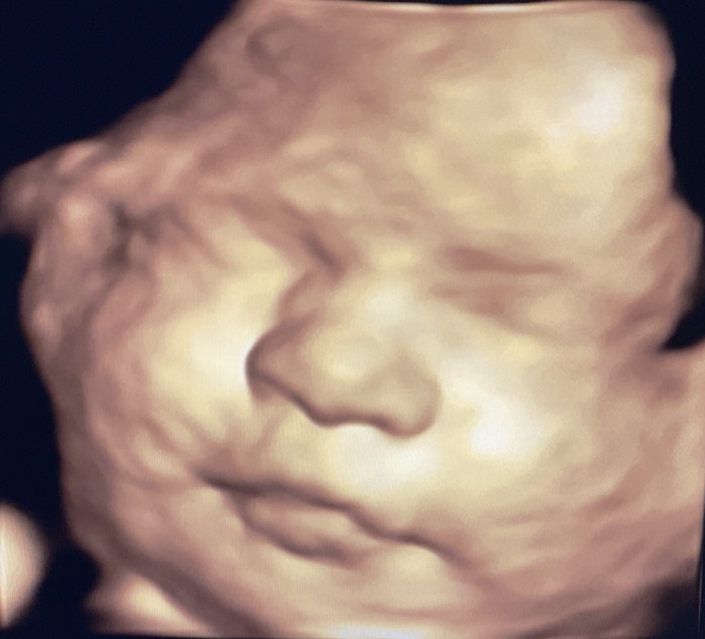

Prenatal Peek®

Prenatal Peek is the leader in 3D 4D Ultrasound. We employ only Certified / Registered Sonographers maintaining unsurpassed standards in 3D ultrasound. You deserve the best! Call us today.